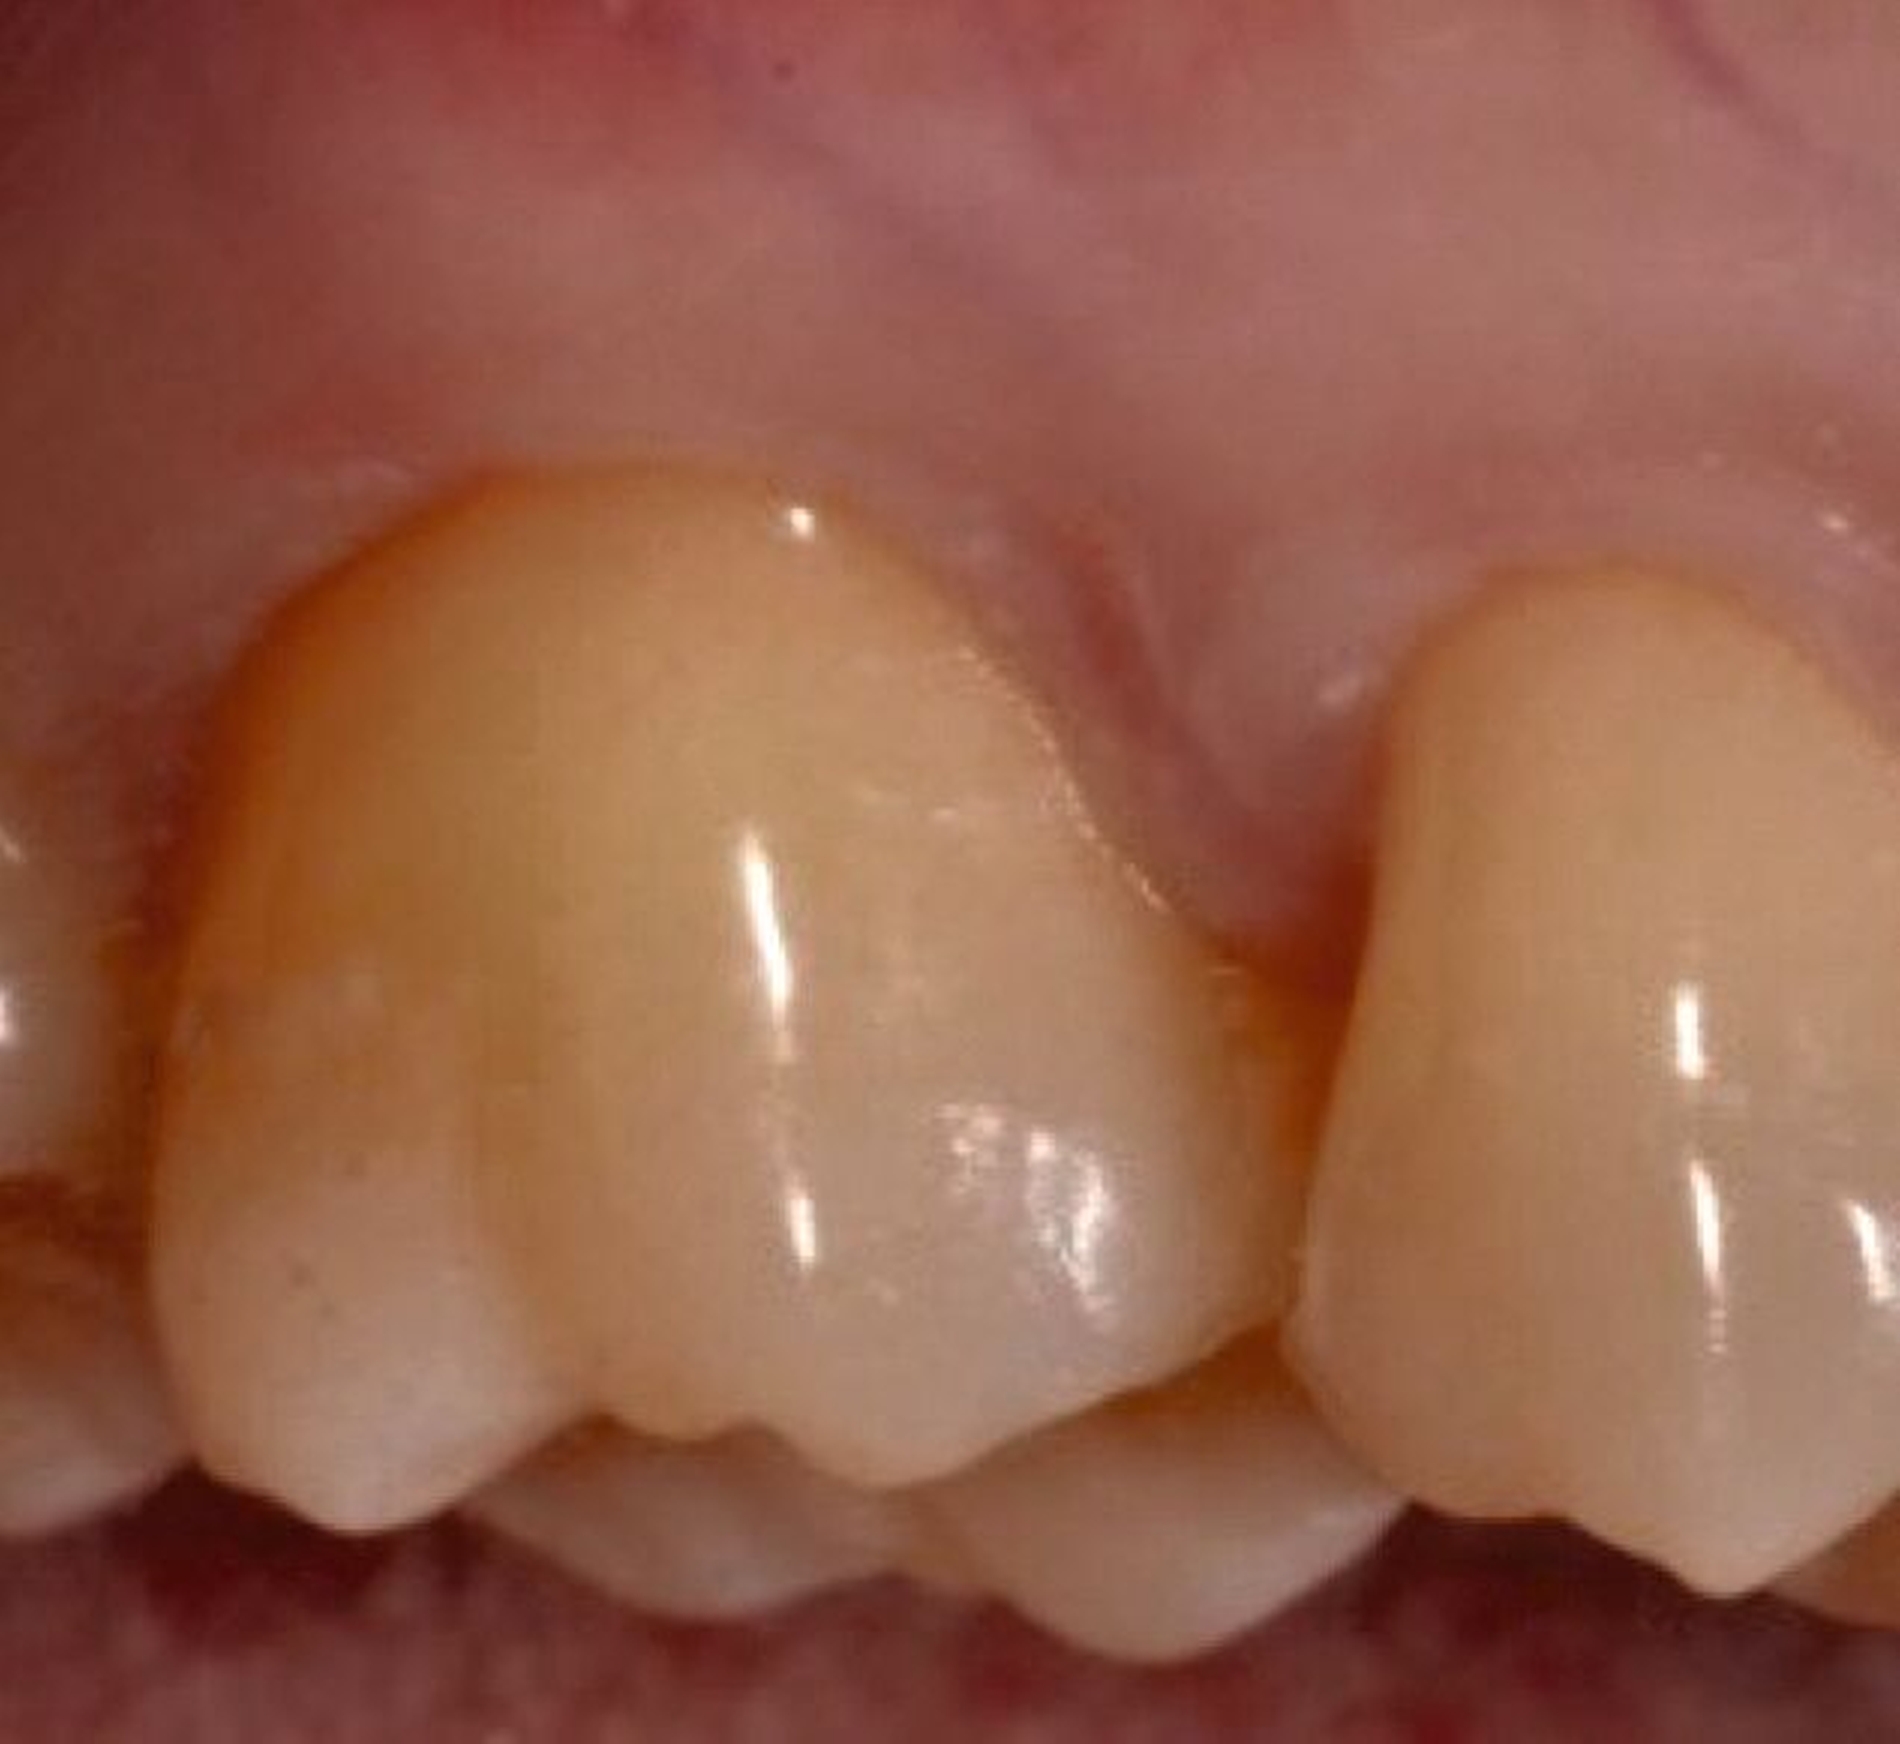

2. Auswahl des Zahnes

Ein adäquater Zugang zum Operationsbereich und auch für die zukünftigen Mundhygienemaßnahmen ist äußerst wichtig. Molaren mit Grad-II-Furkationsdefekten (mandibulär und bukkal maxillär) sind Kandidaten, die für ein regeneratives Verfahren infrage kommen. Basierend auf der verfügbaren Evidenz sind interdentale Grad-II-Furkationsdefekte an Oberkiefermolaren deutlich weniger geeignet, höchstwahrscheinlich aufgrund des eingeschränkten Zugangs. Weitere lokale Charakteristika können Auswirkungen auf die Ergebnisse der regenerativen Furkationschirurgie haben. Zum Beispiel können ein dickerer Phänotyp und das Fehlen einer Weichgeweberezession die Heilung nach GTR-Verfahren positiv beeinflussen. Günstigere Ergebnisse sind an Stellen zu erwarten, an denen das verbleibende approximale Knochenniveau koronal zum Eingang beziehungsweise zum Dach des Furkationsdefekts liegt, verglichen mit solchen, bei denen das approximale Knochenniveau auf der Höhe oder apikal des Furkationseingangs liegt. Ein enger interradikulärer Abstand kann eine gründliche Defektinstrumentierung beeinträchtigen. Das Vorhandensein einer Wurzelkanalfüllung ist nicht per se eine Kontraindikation für die Furkationsregeneration – vorausgesetzt, es gibt keine Anzeichen für apikale pathologische Veränderungen.